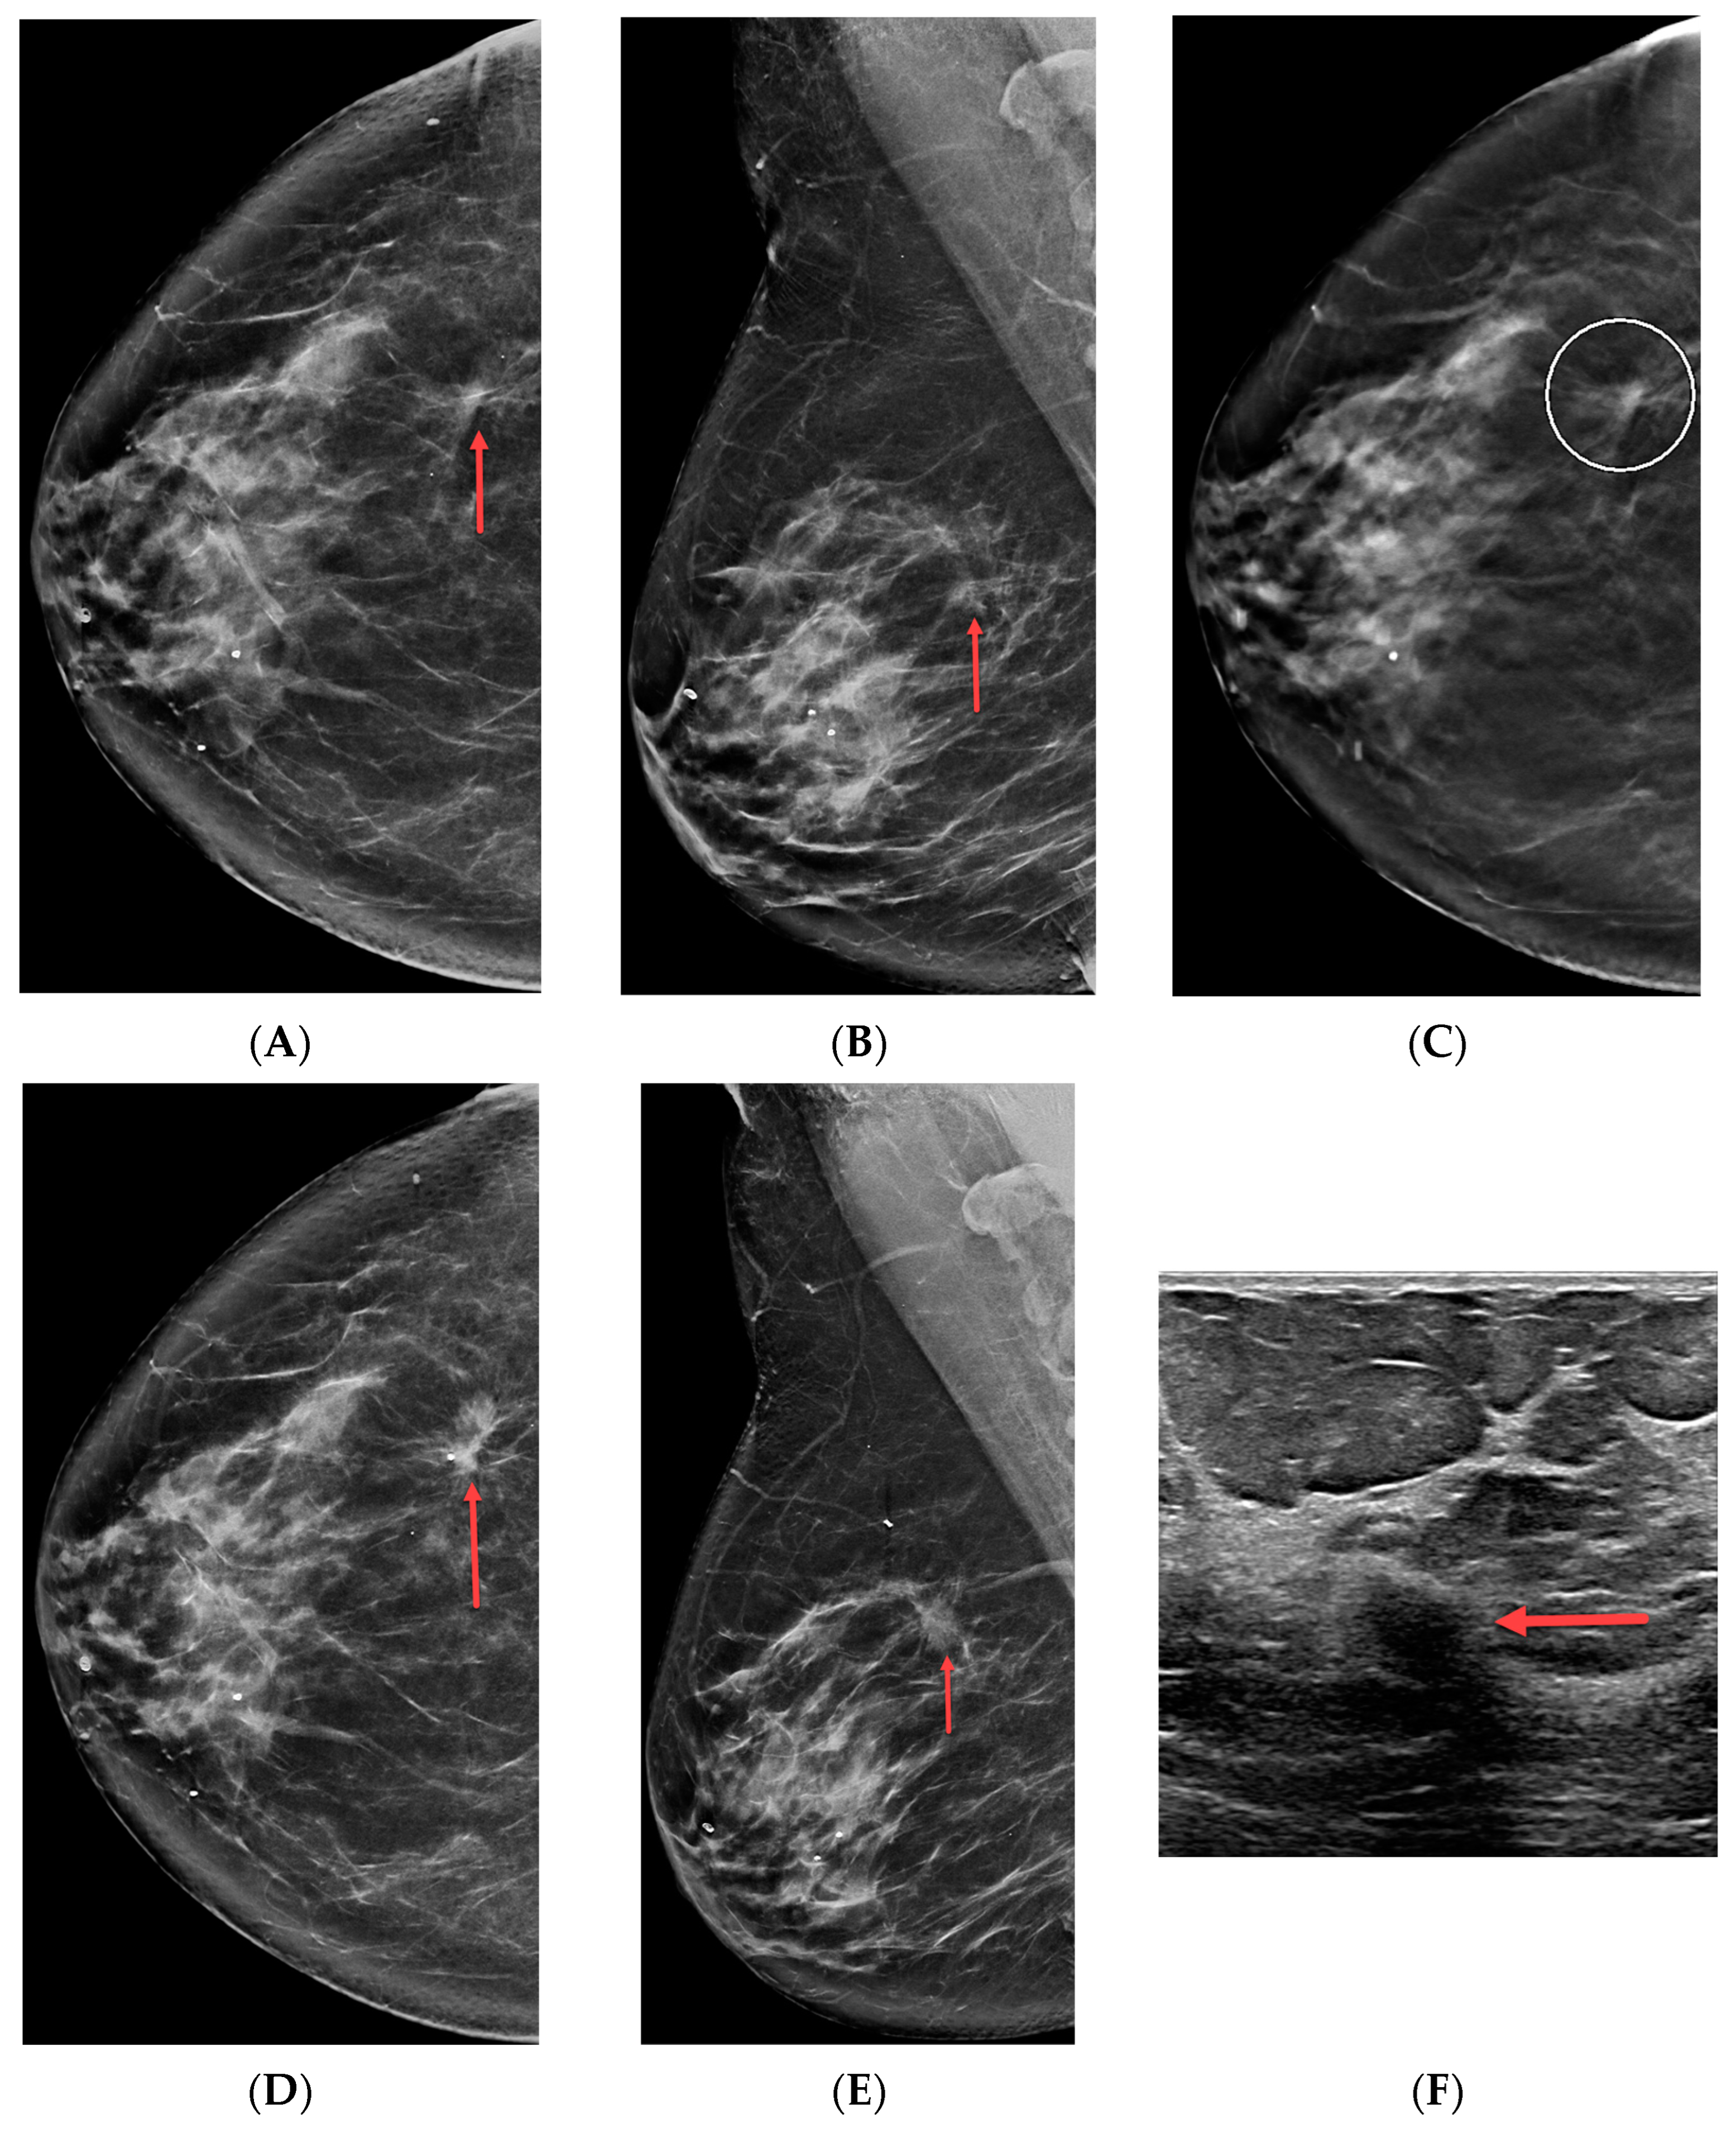

Table 2 compares patient demographics and lesion characteristics based on benign and malignant outcomes. Certain important results deserve specific mention here. First, the likelihoods of malignancy for suspicious masses, asymmetries, and Ads were similar: 29% (37/126), 23% (44/194), and 25% (77/302), respectively (p = 0.40). Increased age was associated with malignancy for each imaging finding type (p ≤ 0.006), and a possible ultrasound correlate was associated with a higher likelihood of malignancy when all findings were considered together (p = 0.012). Two-view asymmetries were more commonly malignant than one-view asymmetries (p = 0.03). Finally, there were two false-negative biopsy results in our study. The first was a suspicious asymmetry biopsied in a 59-year-old female. Biopsy pathology was sclerosing adenosis, which was deemed concordant, but subsequent diagnostic imaging later revealed an invasive ductal carcinoma. The second false-negative biopsy result occurred in a 66-year-old female with architectural distortion that yielded benign fat necrosis at mammographically guided breast biopsy (Figure 2, twelve 9-gauge samples acquired). This result was classified as concordant, but diagnostic imaging less than one year later revealed a mass at the site of the architectural distortion that was found to represent a grade two invasive ductal carcinoma. Calculated sensitivity and specificity are thus, 98.7% and 100%, respectively.

Figure 2. A 66-year-old female with ultrasound-occult architectural distortion. (A) Right craniocaudal synthetic mammogram, (B) right mediolateral oblique synthetic mammogram, and (C) right craniocaudal tomosynthesis slice from 2018 demonstrate suspicious architectural distortion (red arrows and open circle). An ultrasound correlate was not identified, and benign fat necrosis was diagnosed at tomosynthesis-guided biopsy. This result was deemed concordant. The patient’s (D) right craniocaudal synthetic mammogram, (E) right mediolateral oblique synthetic mammogram, and (F) targeted ultrasound from 2019 reveal a grade two invasive ductal carcinoma (red arrows) at the site of mammographic concern from 2018, indicating that fat necrosis was a false-negative biopsy result.